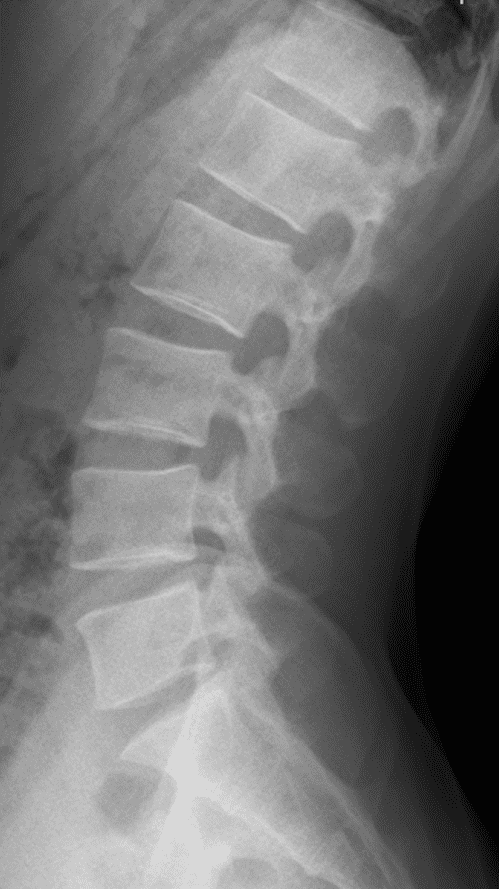

ROI 粗分割例

将 UNet 22通道 版本替换为 UNet ROI 椎骨粗分割模型 + UNet 22通道分类版本,让 ROI 粗分割窗口做先验识别,准确度相比于传统 22通道 UNet 提高约 31% .

因为 UNet 本身并不具备学习线性关系、先验关系的能力,只能在训练阶段通过 Loss 约束各个通道的信息,但是更易使得模型只学习到椎骨的图谱相对位置,并不适合做定位。